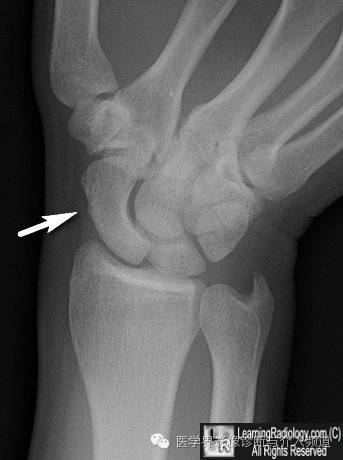

7、舟骨骨赘:舟骨外侧缘细小的骨赘,容易被误诊为骨折。